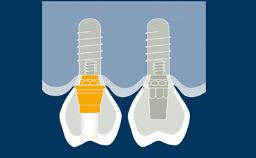

Implantes e suas próteses substituem os dentes. Eles, portanto, têm que participar plenamente da função oral. Uma parte substancial da função oral está relacionada à oclusão quando os dentes e seus substitutos entram em contato. Este módulo examinará a capacidade dos implantes e suas próteses de suportar forças oclusais e oferecer diretrizes para o esquema oclusal.

- reconhecer características de forças oclusais e diferenças biofísicas em como dentes e implantes respondem a eles.

- discutir o impacto potencial das forças oclusais nas complicações e falhas dos implantes e suas próteses.